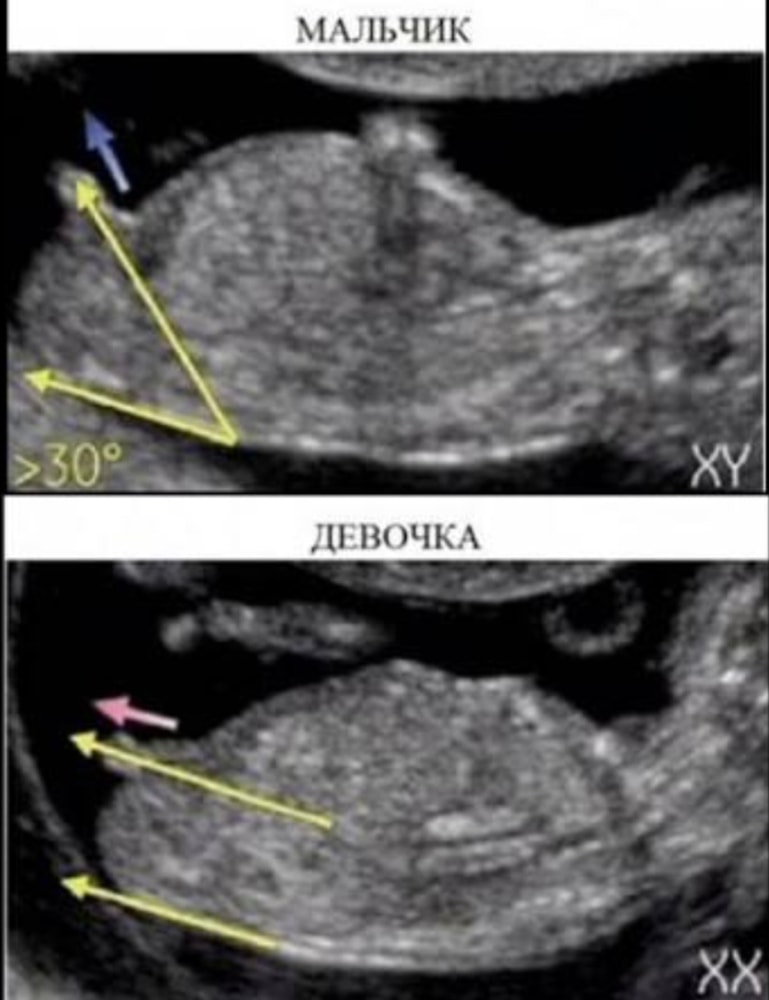

Пол на первом скрининге

прикрепляю вам фотку) может увидите что то

Мне тоже кажется мальчик 🙏😁 Ещё на картинке по нижней линии тела, у мальчиков она такая плавная, а у девочек как дуга )